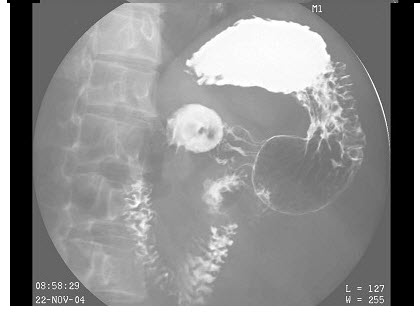

5、单项选择题

男,40岁,黑便1周,半年来呕血两次。查体:脾肋下4cm,结合图像,最可能的诊断为()

A.正常食管

B.食管癌

C.食管静脉曲张

D.贲门癌

E.食管炎

点击查看答案